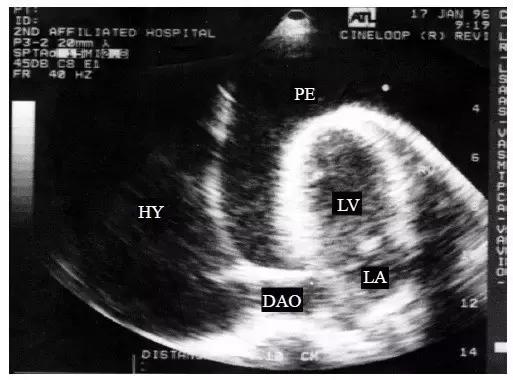

【中量心包积液】

左心室后壁心包腔内液体增多,心尖部也可探及液性暗区,但液性暗区不越过二尖瓣环,未抵达左心房的后方,右心室前壁液性暗区宽度<10mm(图2)。

图2 中量心包积液的二维超声心动图表现

左心室后壁和右心室前壁心包腔内均见液性暗区